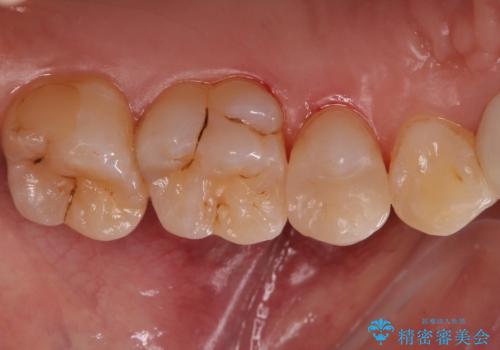

銀の詰め物を白くしたい セラミックインレーでの治療

- 銀歯が気になるためやり替えたいとのことで来院されました。

セラミックインレーで治療を行いました。

- 左上5 セラミックインレー 77,000円費用は治療当時の料金となります

口の中にチラつく銀歯は適合の良いセラミックインレーでやり替えることで綺麗にやり替えることができます。